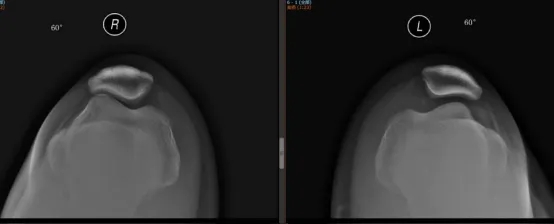

接診的運(yùn)動醫(yī)學(xué)科主任醫(yī)師韋釗嵐博士查體后發(fā)現(xiàn),小張的膝關(guān)節(jié)在屈膝30°位時(shí),髕骨向外側(cè)滑動的幅度很大,向外推動髕骨時(shí),膝關(guān)節(jié)會引發(fā)很明顯的疼痛,再結(jié)合她的X片,考慮為髕骨不穩(wěn)定導(dǎo)致的膝關(guān)節(jié)復(fù)發(fā)性髕骨脫位。

髕骨脫位就是膝關(guān)節(jié)屈伸過程中,髕骨向膝關(guān)節(jié)外側(cè)完全脫出。發(fā)生髕骨脫位的病人一般都會有膝關(guān)節(jié)的外翻或者小腿外旋扭傷的病史。

由于首次脫位的時(shí)候內(nèi)側(cè)髕骨韌帶撕裂,拉不住髕骨,髕骨向外側(cè)脫位;復(fù)位的時(shí)候髕骨與膝關(guān)節(jié)外側(cè)發(fā)生強(qiáng)烈的撞擊,有時(shí)還會伴隨著嚴(yán)重的關(guān)節(jié)軟骨骨折,因此急性髕骨脫位時(shí)疼痛通常比較劇烈,通常會摔倒在地,膝關(guān)節(jié)出血較多,腫脹也比較明顯。